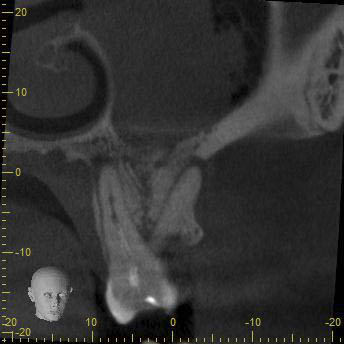

BN2627_DVT (7 von 17) Veröffentlicht 1. Dezember 2014 am 344 × 344 in Unerwartete Anatomie Zahn 26, 27- die WF